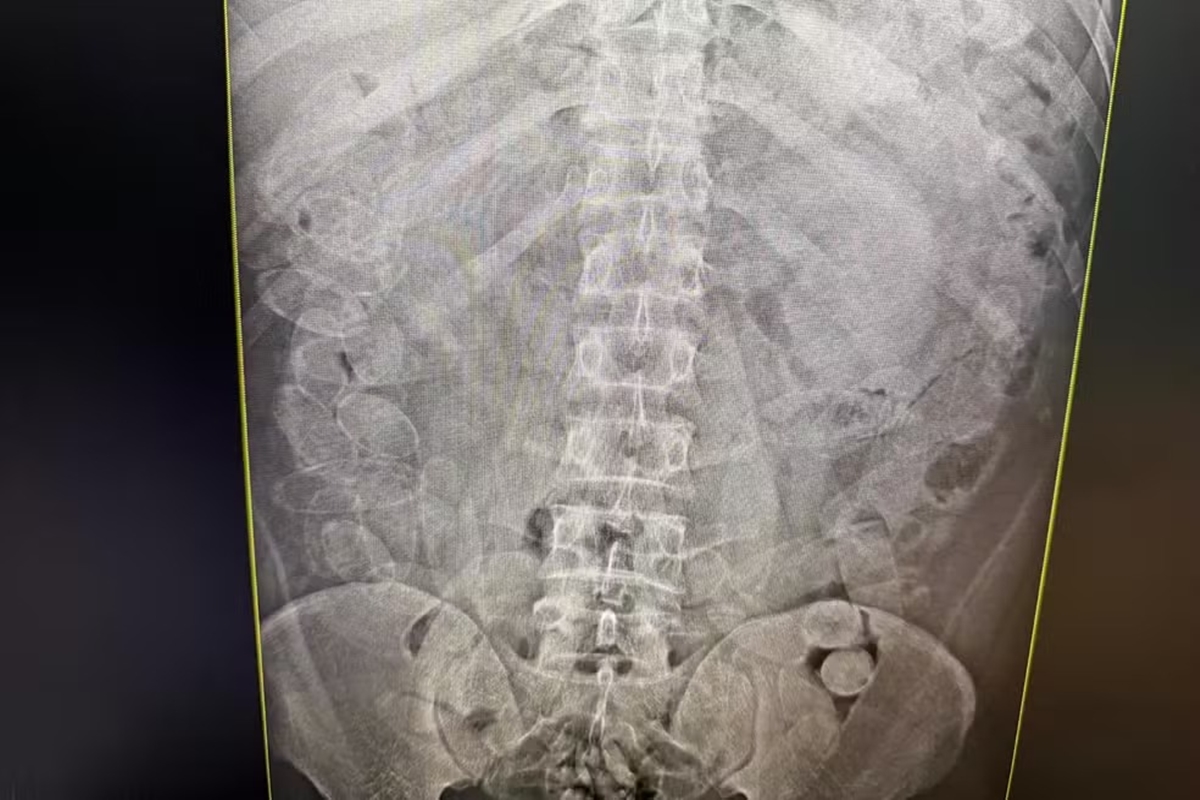

As cápsulas continham substância análoga à pasta-base de cocaína. Parte do material foi encontrada na mochila e na cueca de um dos suspeitos durante a revista. Diante da suspeita de ingestão da droga, os homens foram submetidos a exames de raio X, quando foram avistadas as cápsulas no estômago.